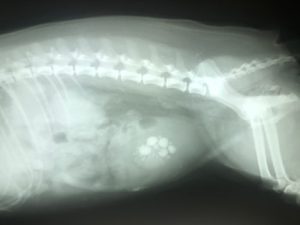

X-ray: some stones will show up on standard x-rays or can be outlined with contrast dye

Ultrasound: urate and cystine